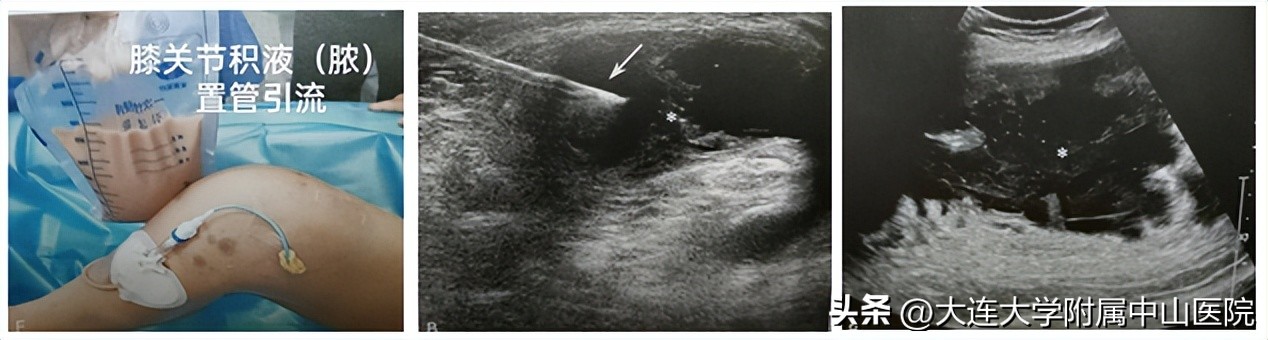

3.超声引导下膝关节腔、滑囊积液(腘窝囊肿、髌前/髌下滑囊炎等)的抽吸及药物注射治疗。